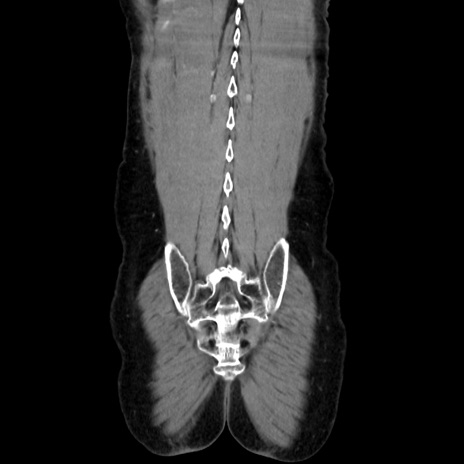

横断像